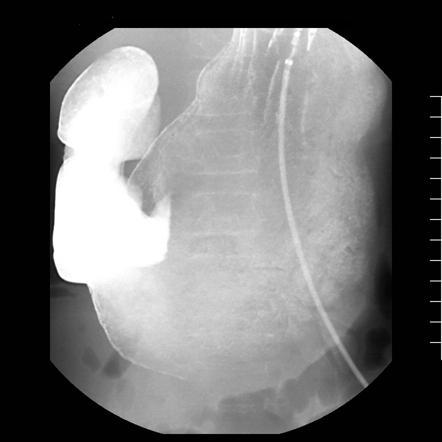

sma syndrome

straight arrow = abrupt cut off of the 3rd portion of the duodenum

curved arrow = incidental duodenal diverticulum